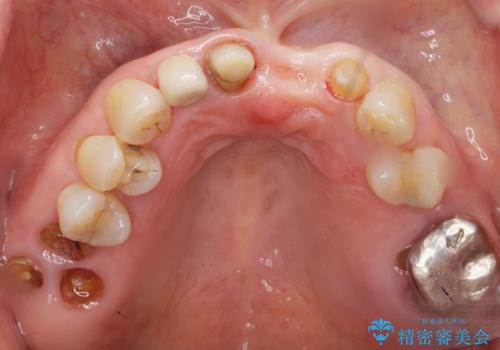

- 上下の前歯が抜けそうだとのことで来院されました。

精査したところ、動揺の著しい上下の前歯は重度の歯周病により保存不可能と判断しました。

ブリッジ、インプラント、義歯の選択肢の中で上下前歯ともにブリッジをご希望されました。

抜歯後歯肉の治癒を十分に待ったのち、ブリッジによる補綴治療を行いました。

歯周病が重度であったため抜歯後の歯肉の陥凹が大きく、GBRや歯肉移植による歯周組織の再建をおすすめしましたが、ご希望されませんでした。

上の前歯の再根管治療もおすすめしましたが、必要性を感じないとのことで土台のやりかえだけをご希望されました。